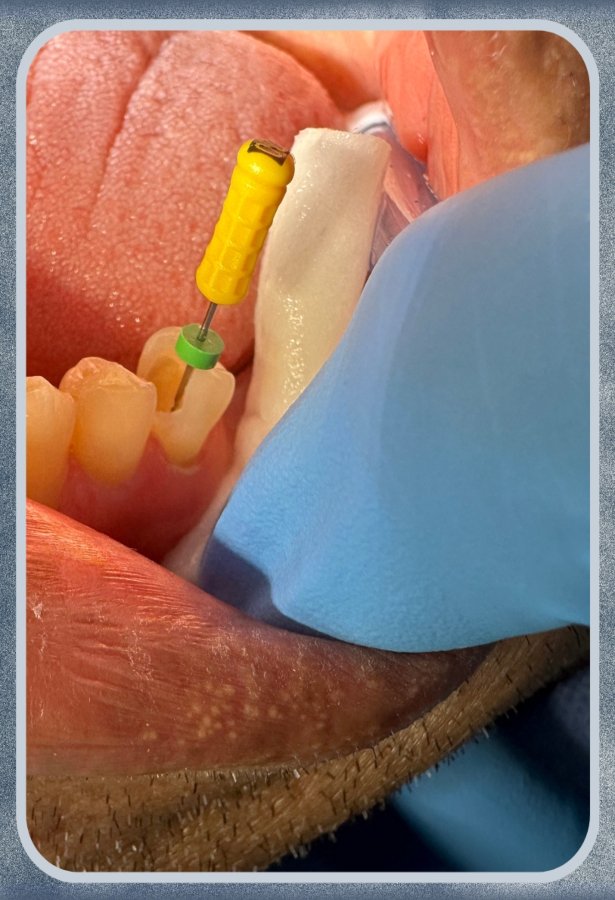

La endodoncia o tratamiento de conductos, es el procedimiento mediante el cual tratamos la pulpa o el nervio que es el tejido blando que se encuentra dentro de los dientes y les pr...